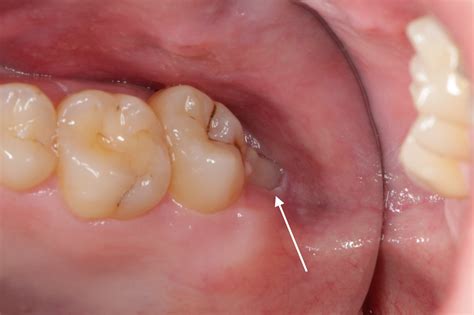

A partially erupted wisdom tooth occurs when the tooth breaks through the gum line but fails to emerge completely into its proper functional position. Instead of sitting flush with your other teeth, a portion of the crown remains covered by a flap of gum tissue, medically known as an operculum. This small flap creates a pocket between the tooth and the gum, which is notoriously difficult to clean.

Because the area is hard to reach with a toothbrush or dental floss, it becomes a magnet for food particles, bacteria, and plaque. This environment is ideal for oral bacteria to thrive, often leading to inflammation, bad breath, and recurrent infections. If left untreated, the issues surrounding these teeth can escalate from minor irritation to severe dental complications.

• A visible flap of gum tissue covering part of the tooth.